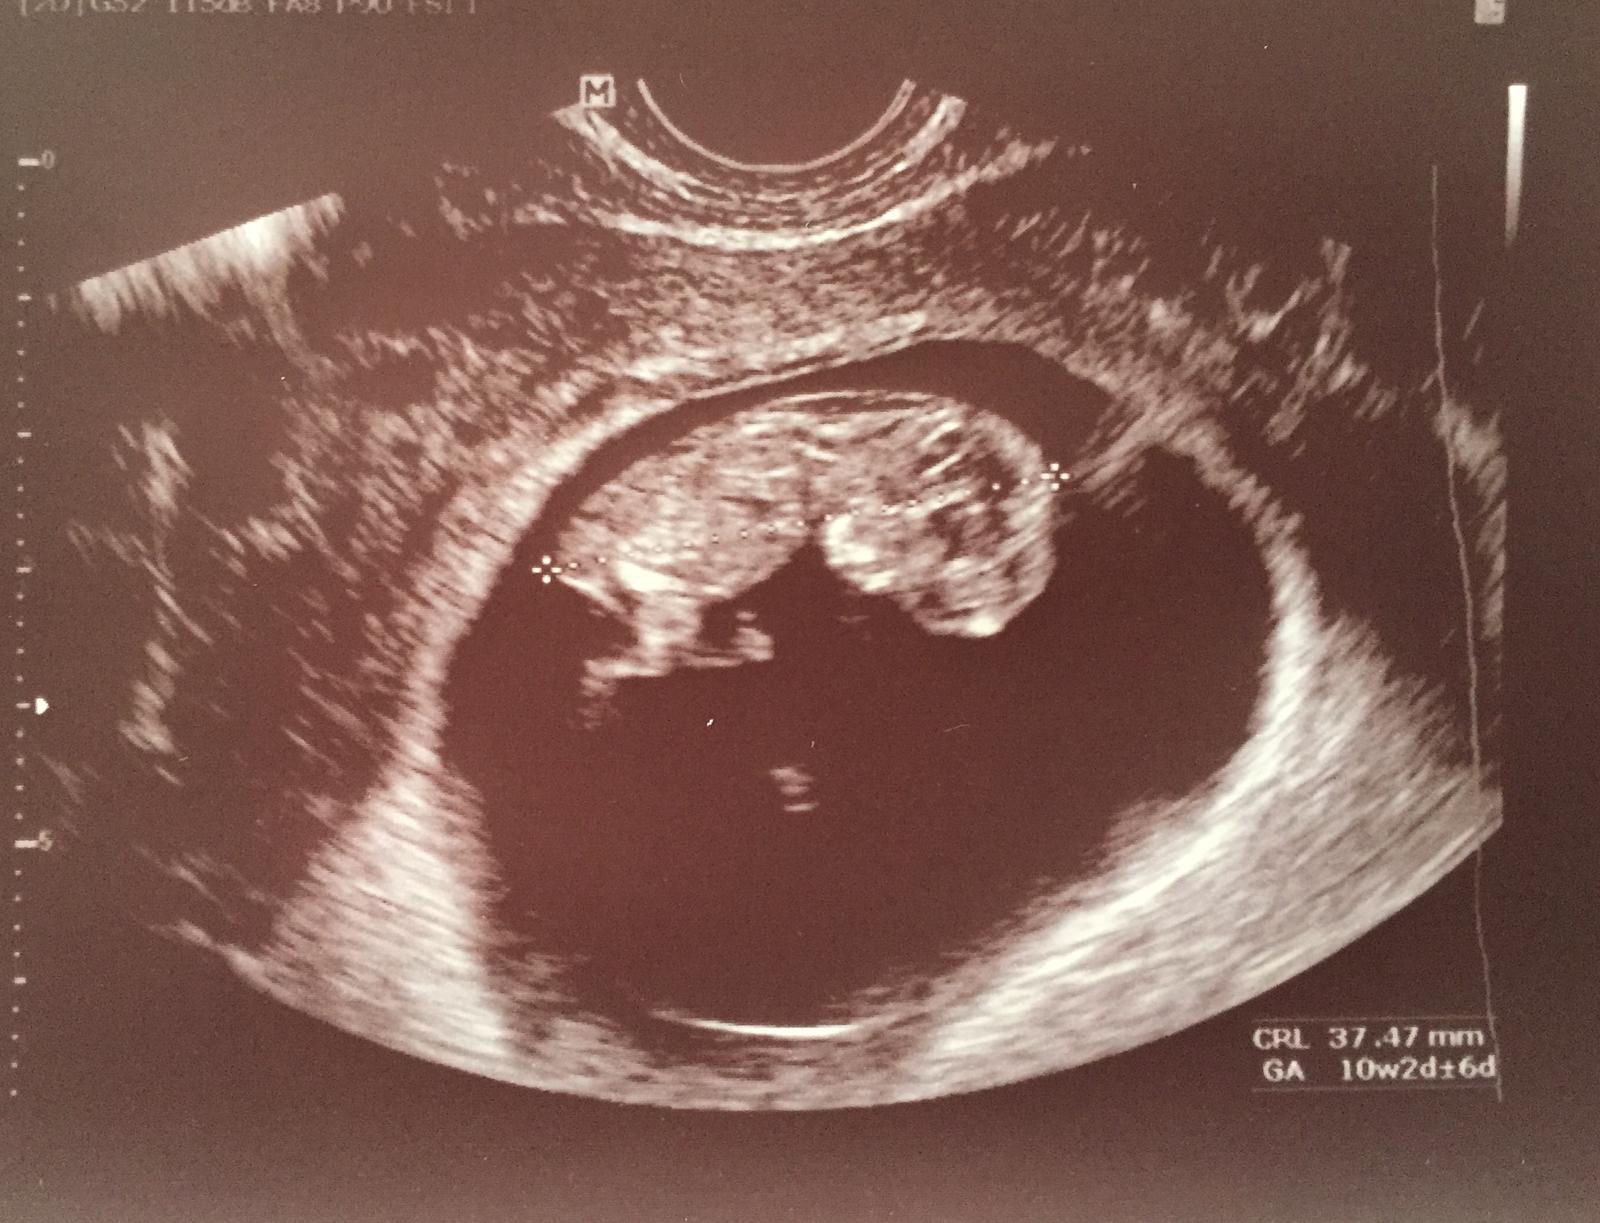

Tak tady je naše fazolka. Má ručičky u hlavy, proto je tak veliká 🙂 Jinak dneska 10+2. Brali mi 5 ampulek krve a na kontrolu za 4 týdny 🙂